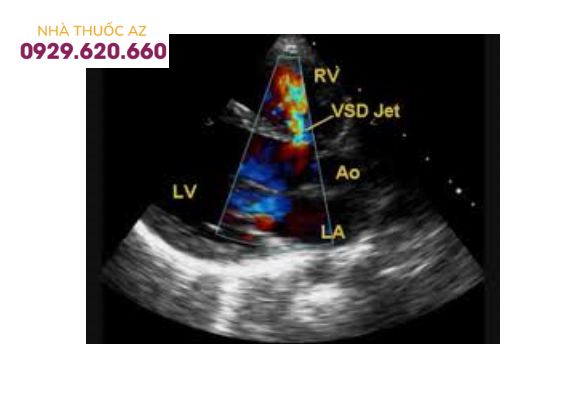

Thông liên thất được phát hiện bằng Doppler mầu (VSD jet): dòng chảy từ thất trái (LV) qua vách liên thất sang thất phải (RV), đi về phía đầu dò được để ở phía thất phải nên có mầu khảm đỏ